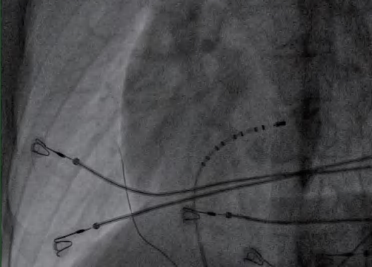

(6)确定室上速类型及异位起源点后,将6F股动脉鞘更换为8F长鞘,在X线透视下将消融导管置入心腔完成射频消融术治疗(图2-2-3)。

图2-2-3 置入消融导管进行射频消融手术